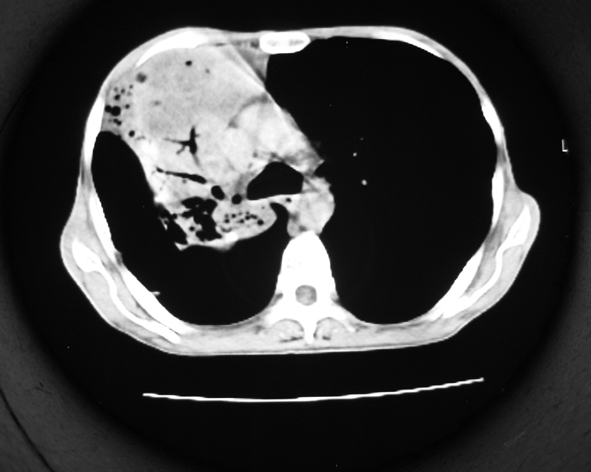

男53岁,咳嗽气短,以往身体健康.

右肺上叶多发多形态空洞及增殖灶,可见团块钙化,胸膜肥厚、粘连,考虑继发型肺结核可能性大

1.右肺上叶干酪性肺炎,2。肺气肿,肺大泡

右肺上中叶结核干酪性肺炎

右肺中上叶干酪性肺炎。

支持右上肺继发性肺结核并干酪性肺炎,右肺大泡,左肺代偿性气肿。